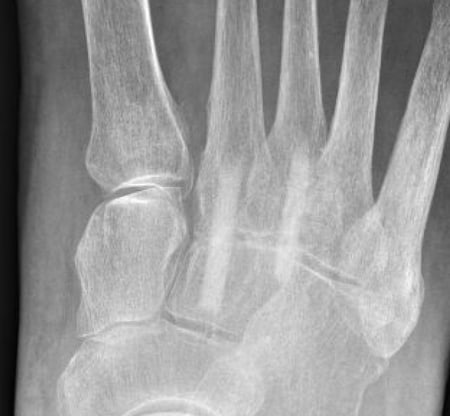

Röntgenbild präoperativ

Im Kontrollröntgen zeigt sich die Arthrose deutlich.